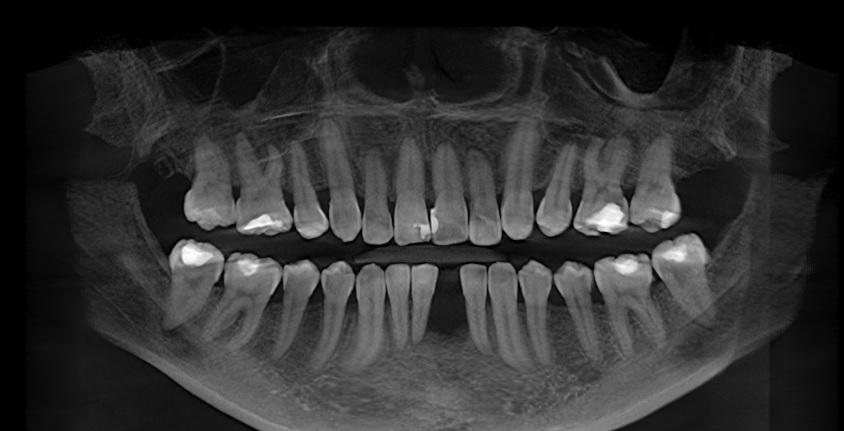

Edit Record Check our patient data records. Add patient information Patient Info Profile picture Last Name First Name Middle Name Birthdate Age Street Barangay City Country Zip Code Contact number Email Procedure 01/30/21 ICF - check up Feb 8,2021 - Implant 11/03/22- OP/OZONE/PAD feb,20,2021- removal of suture march 31,2021- LC 11 & 21 07/31/21 repair 41 zirconia resto 36CAOH/46 CAOH/43/34 OP June 4,2022 - OP / Xray 05/13/23- OP(Moderate); xray; ozone Oct 1 2023 op with air polisher noticed gum recession Removal of fiber splint on 42/43 05/07/24 Air polisher Xray OP 06/15/24 connective tissue graft harvested side: upper right quadrant w/ suture- monofilament absorbable 4/0 donor site: implant #41/32 buccal and lingual combination of monofilament absorbable 4/0 and nylon 6/0 non absorbable 06/22/24 check up 06/29/24 suture removal File raposa_donna_kelly_3.jpg File 2 raposa_donna_kelly_2.jpg File 3 raposa_donna_kelly_1.jpg File 4 donna_kelly.jpg File 5 june_42022.jpg File 6 raposa_donna.jpg File 7 raposa_donna_02.jpg File 8 img_2831.jpg File 9 File 10 File 11 File 12 File 13 File 14 File 15 File 16 File 17 File 18 File 19 File 20 Retain Record Retain Record Yes No Save Your Changes